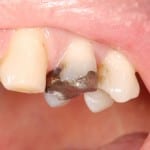

Ceramic Reconstruction step by step

This treatment provides a restoration made of ceramic material as similar to natural tooth (enamel) as anything yet devised. It is suitable for replacing old Crowns, Amalgam (mercury/silver) fillings and will last longer than current white fillings.